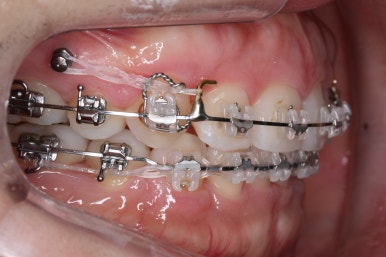

아랫니 모습입니다.

남아있는 발치의 공간이 없어졌으며 큰 이동이 없이 마무리가 되었습니다. 안쪽에는 발치공간이 다시 벌어지지 않도록 유지철사를 길게 연장해서 붙였습니다.

아래쪽의 앞니에는 잇몸뼈가 없기에 자칫 뿌리가 다 드러날 수 있는 위험한 상태였습니다.

다행히도 잇몸이 덮고 있었고 조심스레 마무리를 했기 때문에 추가적인 악화는 없었습니다. 그래도 아래앞니 쪽은 잇몸뼈가 약하기 때문에 평생 조심을 해야 한다며 거듭 말씀드리고 당부 드렸습니다.

앞니, 어금니 맞물림이 좋아진 것을 볼 수 있습니다.

안으로 굽었던 옥니의 각도가 역교정으로 다시 회복이 되었습니다.